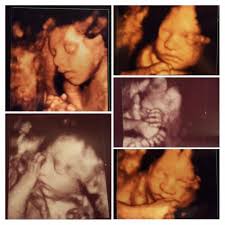

12 Weeks 1 Day Ultrasound Video Dailymotion

12 Weeks 1 Day Ultrasound Video Dailymotion from s1.dmcdn.net